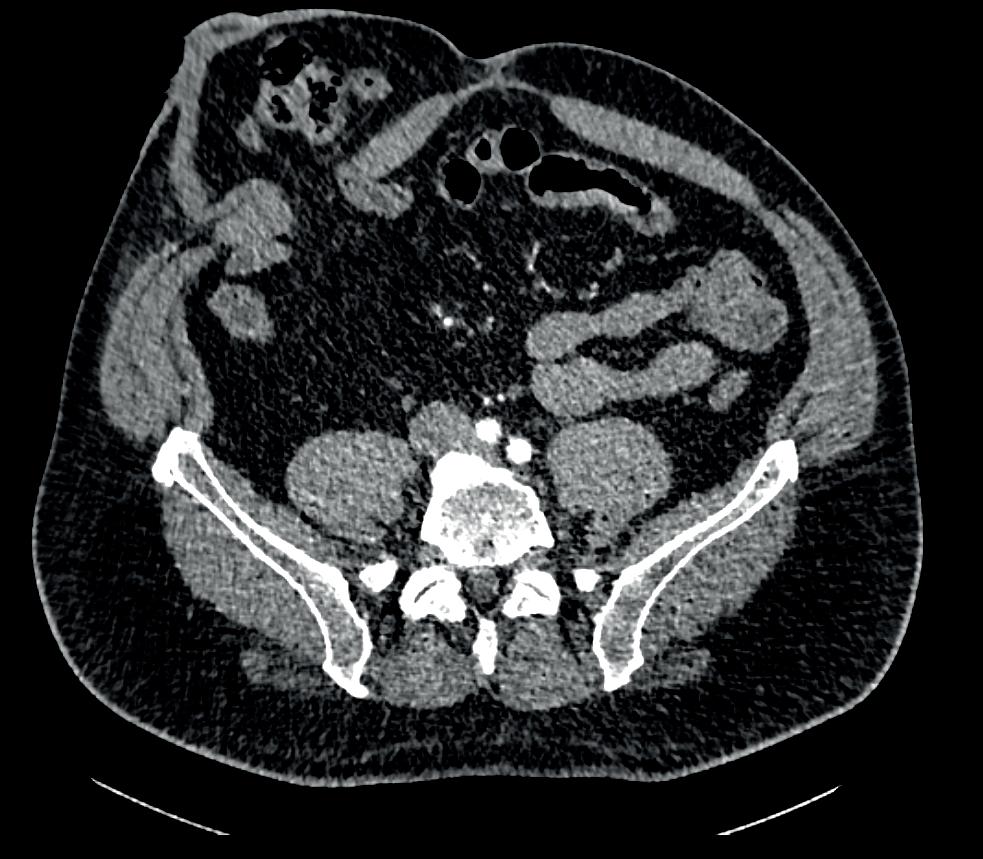

U 3 z nich byl na magnetické rezonanci popsán makroadenom hypofýzy (obr.  1), u 4 mikroadenom a u 4 mužů magnetická rezonance žádný patologický nález neprokázala. Všem mužům bylo provedeno endokrinologické vyšetření.

U 3 mužů byla hyperprolaktiném ie způsobena p ou ze polékově – tito muži užívali ně kte rý typ psychofarmak se schopností blokace dopaminergního tuber oi nfundibulárního systému hypotalamu. Celkem 8 mužům byla nasazena terapie cabergolinem (Dostinex ®) v dávce 0,25–0,5 mg 1– 2× týdně. Celkem 3 muži s prokázaným makr oa denomem byli odesláni k n eu rochirurgickému operačnímu řešení. Závažnost ED jsme hodnotili pět io tázkovou form ou dotazníku Internat io nal Index of Erectile Funct io n (IIEF-5) (obr. 2).

Obr. 1. Makroadenom hypofýzy s výraznou suprasellární extenzí a tlakem na chiasma opticum.

Fig. 1. Pituitary macroadenoma with marked suprasellar extension and pressure on the chiasma opticum.